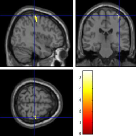

Once the reduced FOV images are available, the proposed pMRI 4D-UWR-SENSE algorithm and its early UWR-SENSE version have been utilized in a final step to reconstruct the full FOV EPI images and compared to the mSENSE Siemens solution. For the wavelet-based regularization, dyadic Symmlet orthonormal wavelet bases [48] associated with filters of length 8 have been used over resolution levels. The reconstructed EPI images then enter in our fMRI study in order to measure the impact of the reconstruction method choice on brain activity detection. Note also that the proposed reconstruction algorithm requires the estimation of the coil sensitivity maps (matrix in Eq. (2)). As proposed in [4], the latter were estimated by dividing the coil-specific images by the module of the Sum Of Squares (SOS) images, which are computed from the specific acquisition of the -space centre (24 lines) before the scans. The same sensitivity map estimation is then used for all the compared methods. Fig. 5 compares the two pMRI reconstruction algorithms to illustrate on axial, coronal and sagittal EPI slices how the mSENSE reconstruction artifacts have been removed using the 4D-UWR-SENSE approach. Reconstructed mSENSE images actually present large artifacts located both at the centre and boundaries of the brain in sensory and cognitive regions (temporal lobes, frontal and motor cortices, …). This results in SNR loss and thus may have a dramatic impact for activation detection in these brain regions. Note that these conclusions are reproducible across subjects although the artifacts may appear on different slices (see red circles in Fig. 5). One can also notice that some residual artifacts still exist in the reconstructed images with our pipeline especially for . Such strong artifacts are only attenuated and not fully removed because of the high level of information loss at .

| mSENSE | 4D-UWR-SENSE | ||